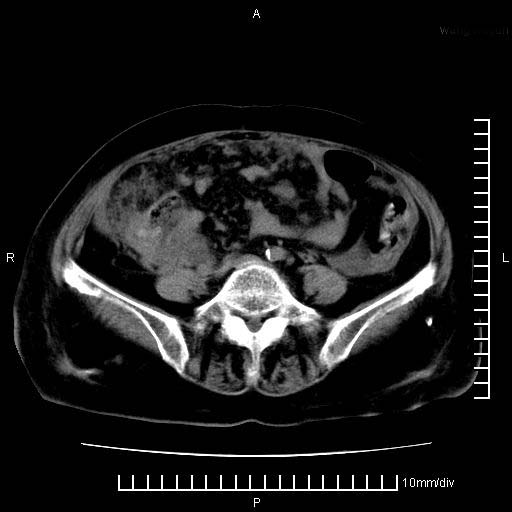

标题: CT28280:腹部增强:女性,80岁

上腹疼痛月余,外院核磁诊断胰腺癌。现临床示右下腹可明显触及包块,可片子上怎么没有看到?

胰腺体部癌累及周围器官,腹膜、粘连,临床摸到的可能是粘的组织

胰腺结构模糊,胰尾部见囊性包块,周围脂肪密度增高,左肾前筋膜增厚,胸水、腹水。不符合胰腺ca伴腹膜腔转移。考虑胰腺炎伴假性囊肿形成、胸腹腔积液。

1、考虑胰腺癌伴腹膜腔转移,胸腹水。

1)考虑胰腺癌并胰腺假性囊肿形成。2)肝内低密度灶,不排除转移。3)右肾盂积水。4)腹水。5)右侧胸腔积液并右肺下叶部分膨胀不全。

考虑胰腺ca伴腹膜腔转移、肝左叶转移、右肾积水。右胸腔积液。